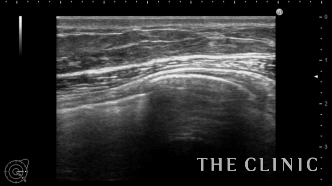

本日紹介する方は左胸の痛みで来院、見た目や触診では問題ありませんでしたが、エコー検査で左胸のバッグが破損していました。エコー所見です。右は軽度のカプセル拘縮を認めますが、左は破損してカプセル内にシリコンが漏れていました。腋の下からバッグを取り出しましたが、左のカプセル内にはシリコンが漏れていました。

バッグの破損があると術後にカプセル内にリンパ液が貯留する場合がありますが、

1週間後のエコーではリンパ液の貯留もなく問題ありませんでした。バッグの破損は自覚症状がない場合も多いので、定期的にエコー検査をするべきだと思います。